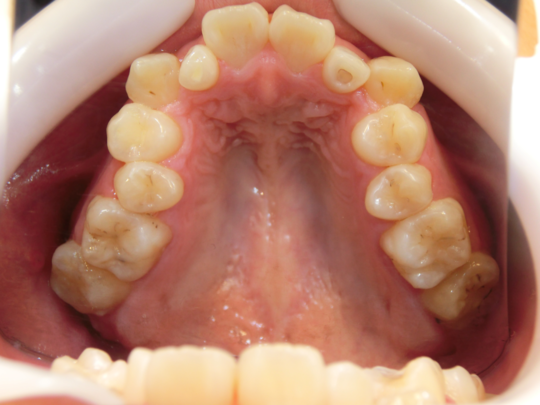

治療前

治療説明 歯科矯正でも目立ちにくい矯正方法であるマウスピース矯正で治療しました

治療期間 1年9か月

治療費用498000 円